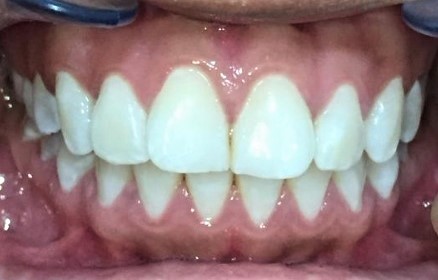

Classe II div 1, articulé croisé postérieur, surplomb accru, déviation de la ligne médiane maxillaire, rotations d'encombrement

Résultats obtenus

- Relation de classe I obtenue

- Guidage fonctionnel des canines des deux côtés

- Articulé postérieur corrigé

- Surplomb et recouvrement normaux obtenus

- Surplomb amélioré

- Lignes médianes coïncidentes

- Bonne inclinaison axiale des incisives

- Courbe de Spee nivelée

- Forme de l'arcade améliorée

- Cas où tous les objectifs du traitement ont été atteints

- Des arcades harmoniques ont été obtenues

État initial

État final